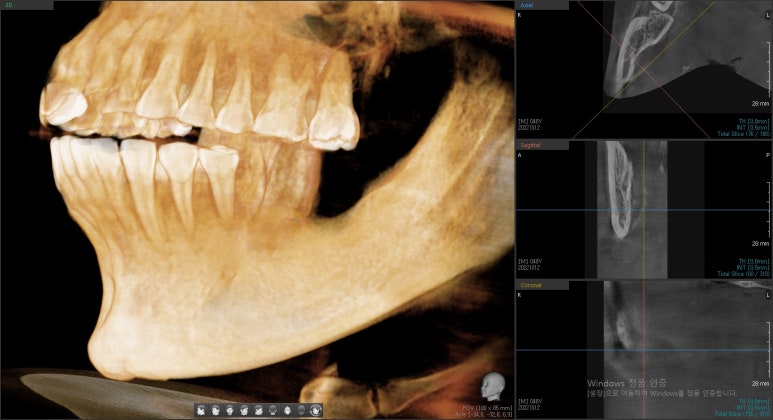

- 긴 브릿지가 흔들려요 → 여러 개 임플란트 수술 및 상악동거상술

치아 여러개를 연결시킨 브릿지가 오래 되어서 흔들려요

라며 찾아오신 환자분입니다.

여러개 임플란트를 동시에 하는 수술이고

환자분도 겁이 많아 수술시간이 짧게 끝나는 걸 원하셔서

네비게이션 임플란트로 시행하여 빠른 시간에 수술을 끝낼 수 있었습니다.

상악동 거상술 뼈이식도 같이 진행하였습니다.